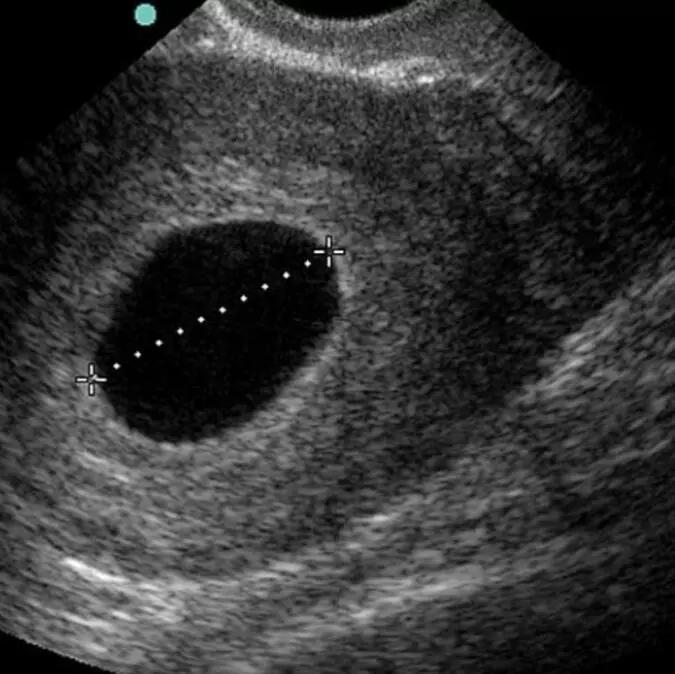

说一位孕事粉丝妈妈的经历:在孕6周的时候检查出有胎心,各项指标都正常,到第8周突然见红,去医院检查宝宝没胎心了,8W+2做的人流手术,时间也定格在8W+2,这是我们一起走过的日子。